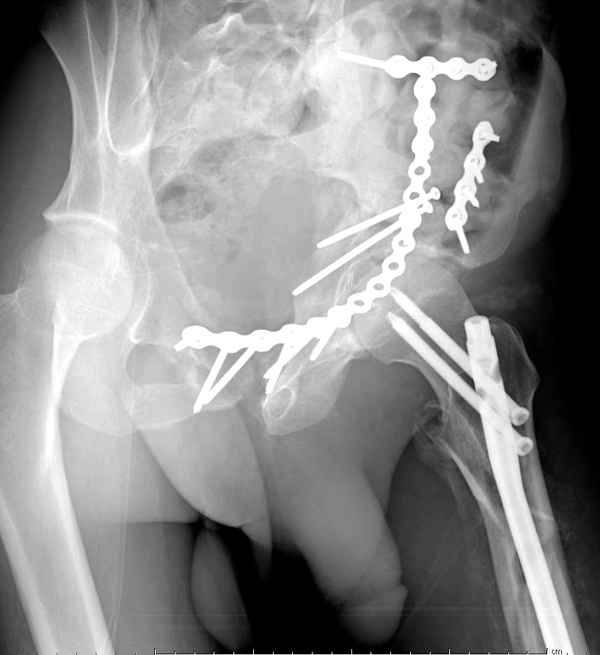

А что Ввам не понятно? И что Вам дадут нового в понимании паттерна данного повреждения "стандартные проекции"? Согласен! Есть детали, которые требуют осмотра пациента, но это детали. А тактика, как уже и говорилось: Реконструкция, потом эндопротезирование. Доступ... Впрочем, нагляднее посмотреть презентацию (прикрепленный файл). В представленном случае все делалось одномоментно - реконструкция и эндопротезирование. Доступы сочетались (задний и подвздошно-паховый). В данном же случае желательно выполнить в 2 этапа.

понимание Классификации Летурнеля позволило бы вам скорее всего выполнить реконструкцию под эндопротез из одного стандартного доступа в одну сессию, а не из двух с непонятным отпиливанием крыльев. Два доступа имели бы смысл, если бы планировалась полная реконструкция сустава в расчете на его функционирование его какое-то время. Представленный вами случай задает больше вопросов, чем ответов. Стоило затевать такую реконструкцию, чтоб установить обычную цементную чашку. Зачем 2 этапа для первичного эндопротезирования?

Из какого одного "стандартного" доступа вы собираетесь выполнить реконструкцию спустя 3 месяца? Из расширенного подвздошно-бедренного или У-образного с flip остеотомией большого вертела. В обеих случаях, скорее всего, разрез будет в проекции послеоперационного рубца. А мы даже пациента не видели. А задние отделы?!!! Надо фиксировать или нет? А если надо, то как, каким доступом? У "непонятного" отпиливания крыла - есть вполне понятные причины и обоснование. Это не ново! Или перкутанно фиксировать КПС? (спустя 3 месяца)!

А почему в 2 этапа? Исключительно для установки press-fit, а не обычную цементную чашку в реконструированную первым этапом и сросшуюся вертлужную впадину.

Здесь несколько вариантов двухколонных свежих переломов, которые были оперированы из одного-заднего, а также из двух: переднего и заднего доступов.